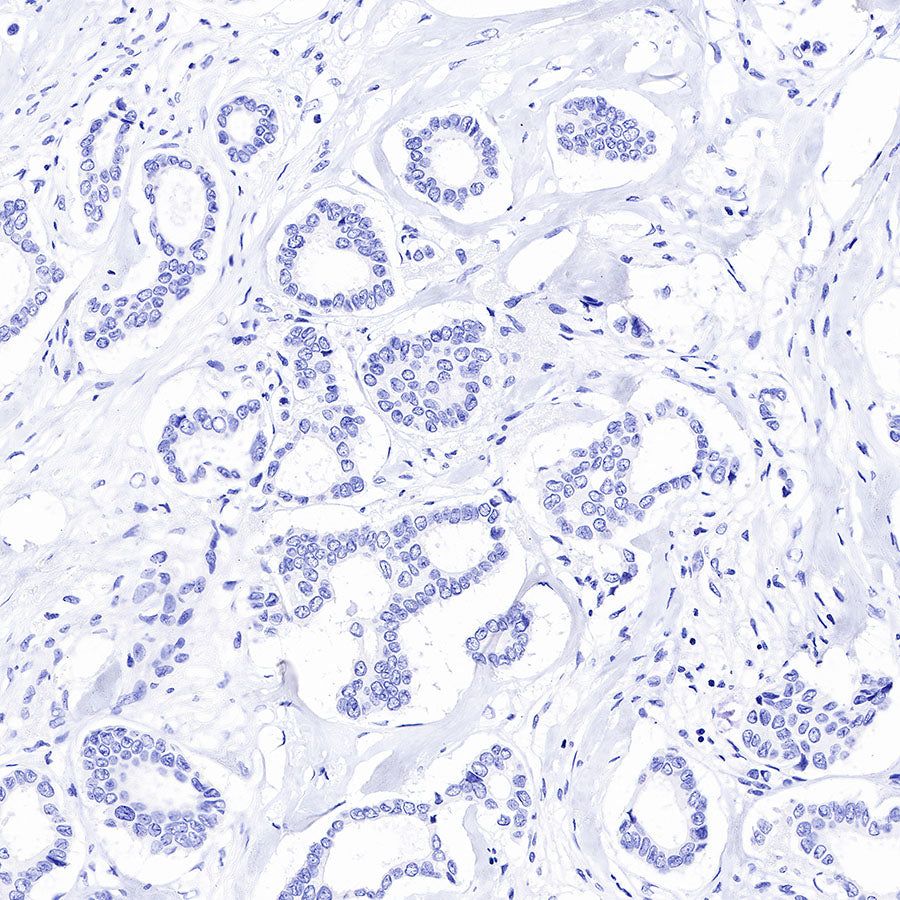

Immunohistochemistry

Negative control: IHC shows negative staining in paraffin-embedded human breast cancer. Anti-PSA antibody was used at 1/1000 dilution, followed by a HRP Polymer for Mouse & Rabbit IgG (ready to use). Counterstained with hematoxylin. Heat mediated antigen retrieval with Tris/EDTA buffer pH9.0 was performed before commencing with IHC staining protocol.